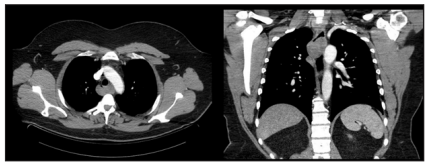

A 44-year-old male with a history of HTN presented with progressive dysphagia to solid food over the last 6 months. Physical examination, vital signs and initial basic laboratory work up were largely unremarkable. CT scan of the chest with contrast revealed a 4cm x 4cm posterior mediastinal mass at C2-C4 levels behind the trachea, with resultant distortion of the esophagus (Figure 1). Endoscopic ultrasonography (EUS) revealed extrinsic compression in the upper third of the esophagus by a large hypoechoic lesion (Figure 2). Fine needle aspiration (FNA) was performed with cytology revealing smooth muscle tumor with nuclear atypia raising concern for leiomyoma (Figure 3). As a result, patient was referred to our Cardiothoracic Surgery Team for surgical excision (Figure 4).

Figure 1: Contrast-enhanced computed tomography (CT) revealed a 4 cm x 4 cm posterior mediastinal mass at C2-C4 levels behind the trachea.